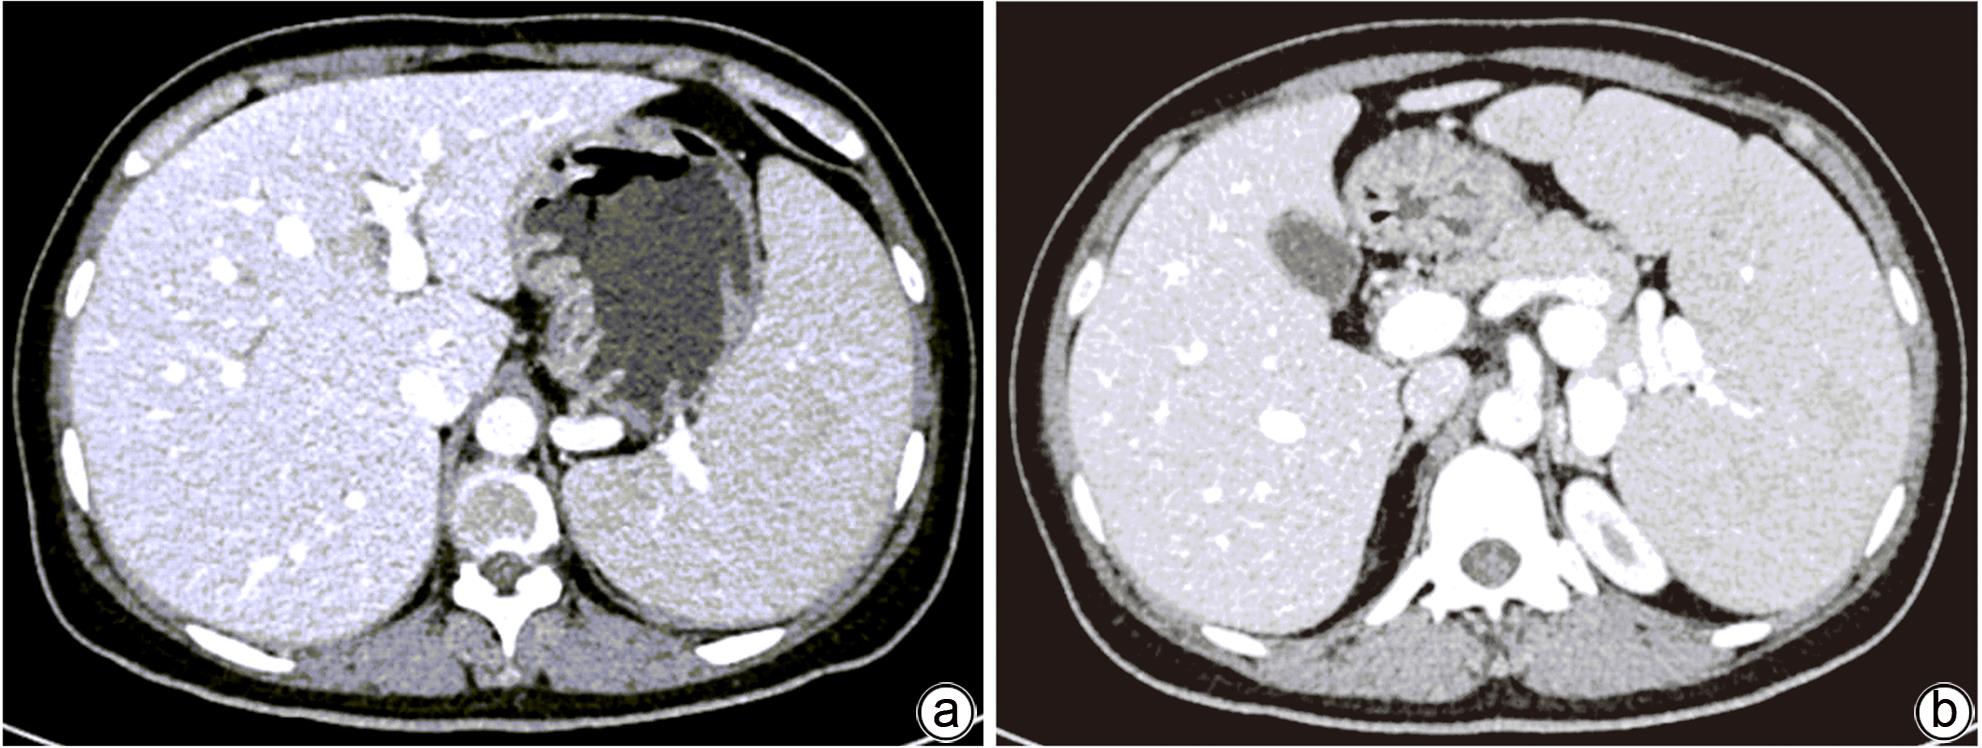

摘要: 本文报道以“肝脾肿大待查”为主诉,经各项检查确诊为B型尼曼-皮克病的案例,并通过文献复习,总结B型尼曼-皮克病肝脏受累的异质性表现,旨在提高疑难罕见肝脏疾病的临床诊治水平。

Abstract: This article reports a case with the chief complaint of “hepatosplenomegaly to be investigated” and a confirmed diagnosis of Niemann-Pick disease type B after various tests, and a literature review was conducted to summarize the heterogeneous manifestations of liver involvement in type B Niemann-Pick disease, in order to improve the clinical management of difficult and rare liver diseases.-